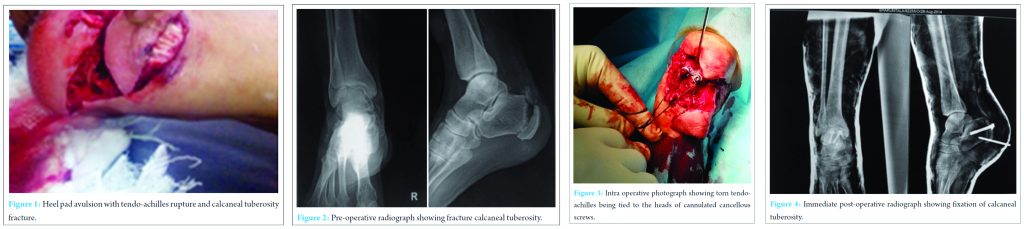

A 63-year-old woman presented with injury to right ankle after a road traffic accident. Following initial resuscitation and stabilization of the patient, assessment for other injuries was done. Physical examination showed right heel pad avulsion as shown in [Fig.1]. The extent of the wound contamination, soft-tissue loss, skeletal injury, and sensation and viability of the avulsed flap was done. Wound was contaminated and there was no skin loss. Radiographs were obtained to identify the skeletal injury which showed fracture of right calcaneal tuberosity as shown in the [Fig.2]. Finally, the compound fracture was classified according to Gustilo-Anderson classification as grade IIIA. Broad spectrum antibiotics with gram positive, gram negative and anaerobic coverage were started intravenously. The patient was counseled about the potential complications of re-implantation of heel pad and the possible necessity for additional surgical procedures. Under regional anesthesia, the wound was debrided and thoroughly lavaged. Fixation of the calcaneal tuberosity was done temporarily with kirschner wires, followed by two 4.5 mm cannulated cancellous screws. But final tightening of the screws was not done. Tendo-achilles was sutured using Ethibond no 5 suture with Krackow`s technique and the two ends were tied to the head of the screws over washers. Once properly tied, the final tightening of screws was done. Thus giving a secure fixation to calcaneal tuberosity and tendo-achilles [Fig. 3]. The heel pad was later fixed using Schanz pin in the centre and primary suturing of the wound was done [Fig. 4]. This provides a stable anchorage for the heel pad over the calcaneus.